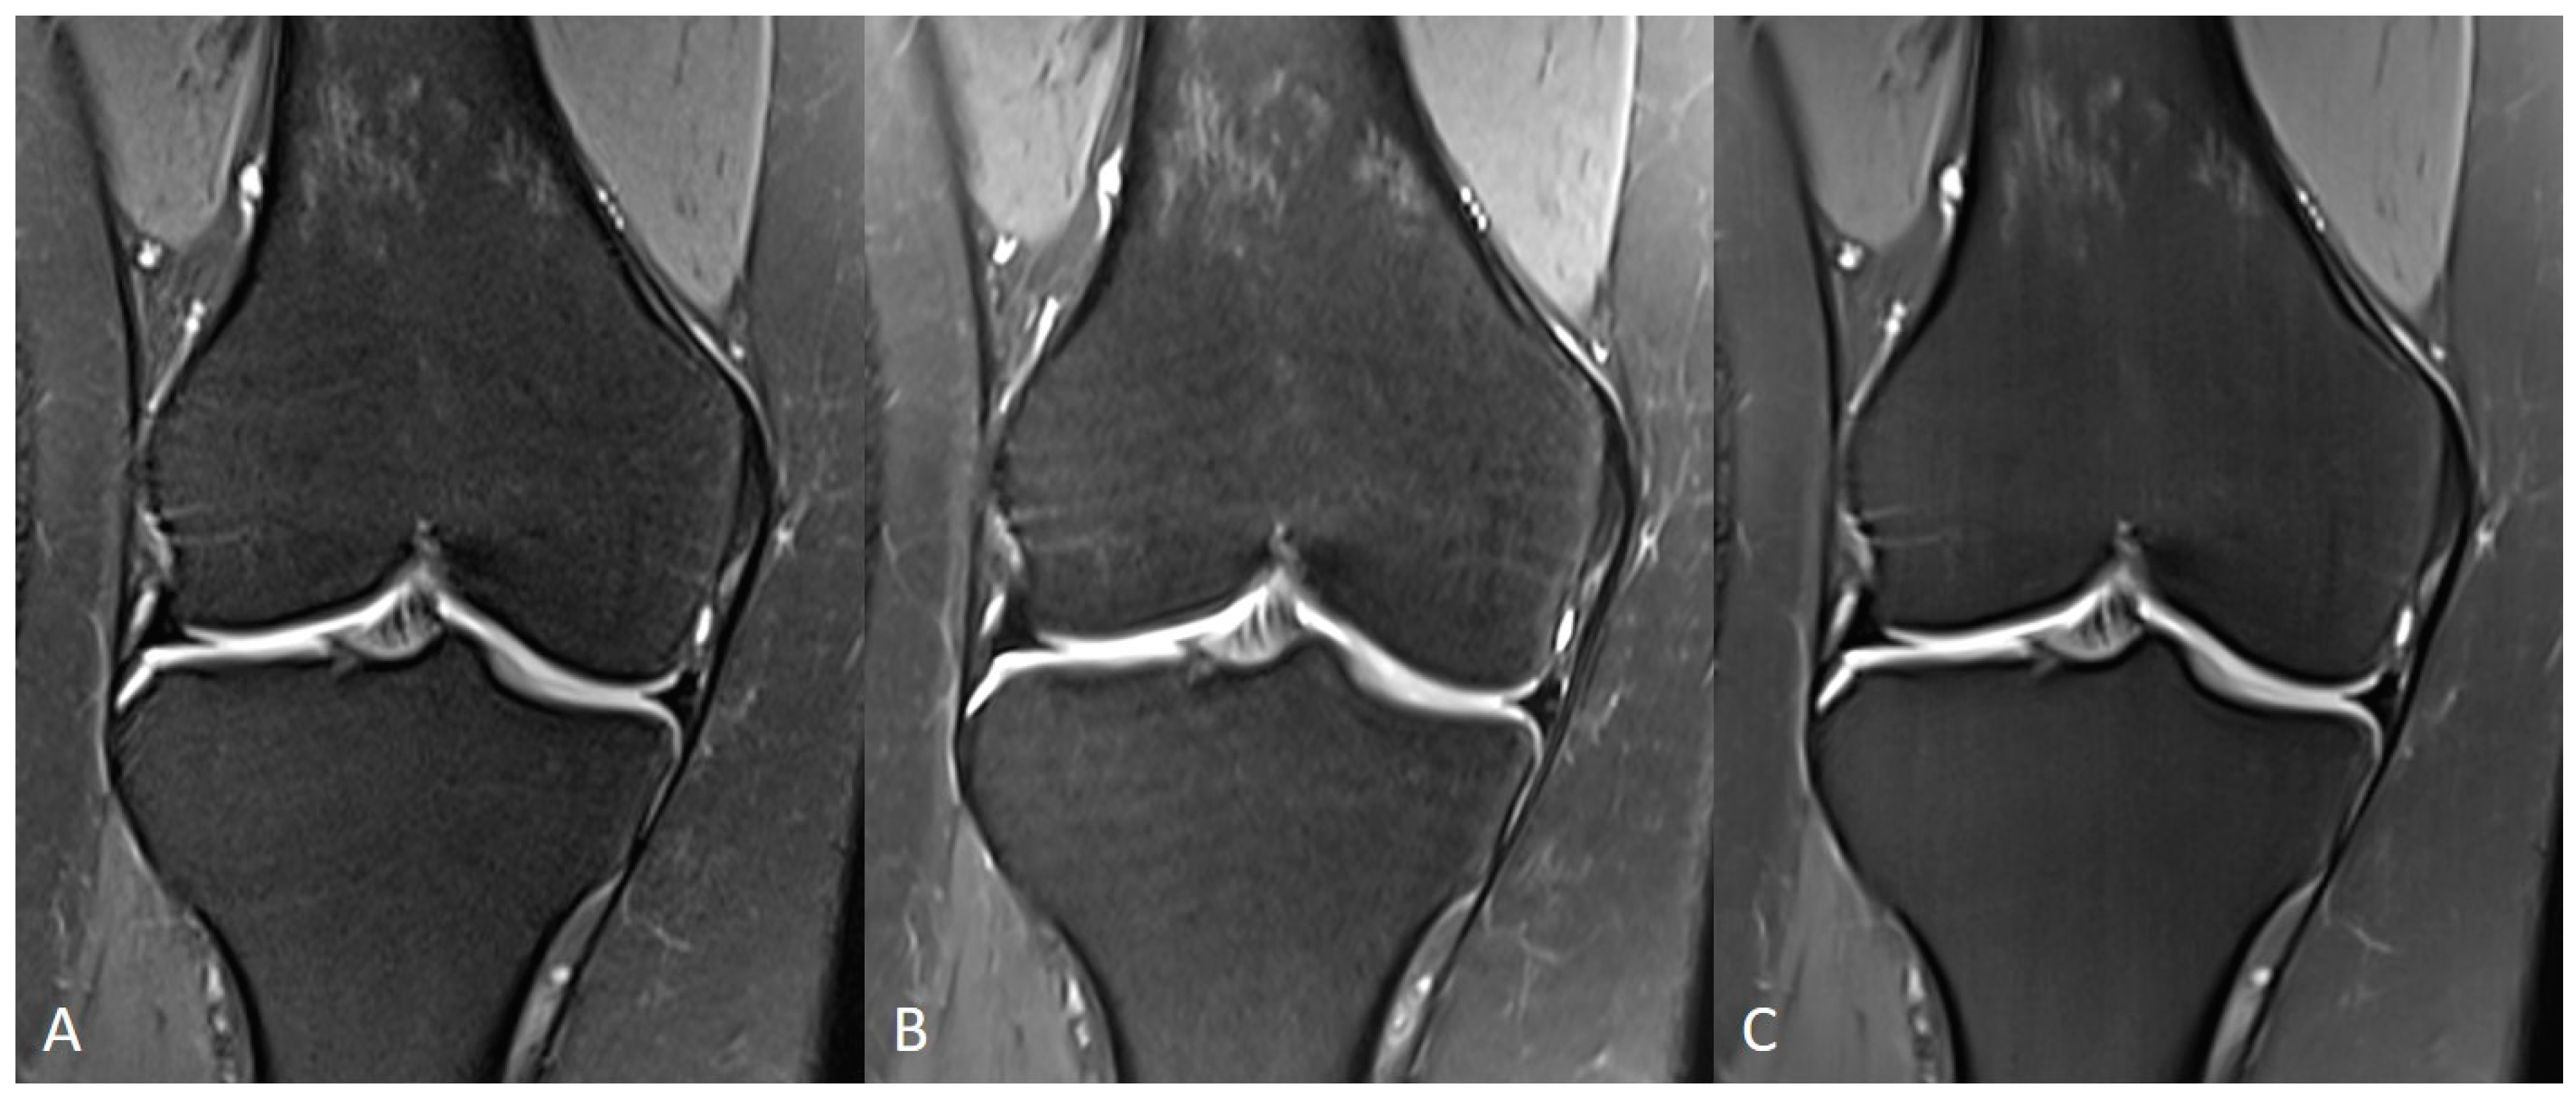

| Knee | TSES | TSE PD FS | coronal | 3:11 | 150 | 0.2 × 0.2 × 3.0 | 2 | 1 | 3 | 3790 | 44 | 150 | 100 | 14.6 |

| sagittal | 3:11 | 150 | 0.2 × 0.2 × 3.0 | 2 | 1 | 3 | 3790 | 44 | 150 | 100 | 14.6 | |||

| TSEDL | TSE PD FS | coronal | 1:33 | 150 | 0.5 × 0.5 × 3.0 | 1 | 1 | 3 | 3580 | 41 | 150 | 120 | 13.7 | |

| sagittal | 1:33 | 150 | 0.5 × 0.5 × 3.0 | 1 | 1 | 3 | 3580 | 41 | 150 | 120 | 13.7 | |||